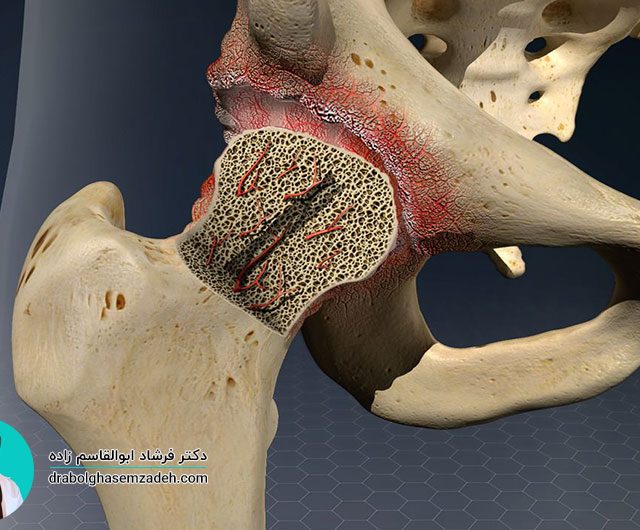

یکی از بیماری های مفصلی پا علائم شدید و ناگهانی به همراه دارد، بیماری نقرس است. عوامل متعددی باعث افزایش این بیماری پیچیده آرتروزی در بیماران به خصوص مردان می شود. به دلیل حملات و درد ناگهانی که بیماری نقرس دارد، تحمل آن می تواند بسیار رنج آور و دردناک باشد. شناخت علائم بیماری نقرس […]...